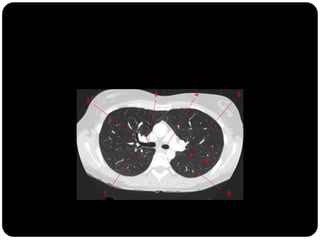

Em que lobo está essa lesão?

Resposta: LID

Importância do

perfil;

Importância da

ausência do sinal da

silhueta;